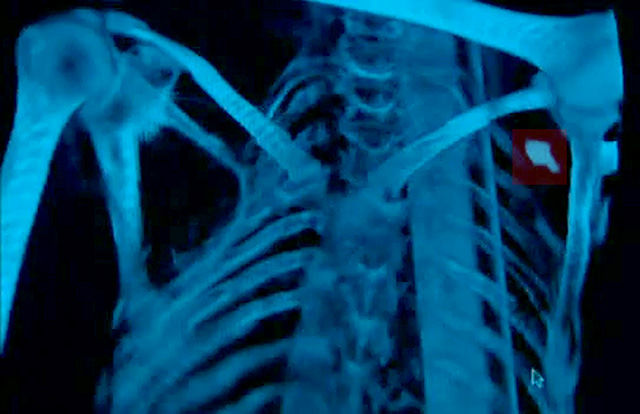

- Una punta de flecha de pedernal, alojada entre la clavícula y la espátula de su hombro izquierdo (ver imagen)

Análisis de los diferentes pólenes en su ropa y su estómago demostraron que estaba lejos de su lugar de origen y que murió en primavera. Un estudio de mayo de 2012 concluyó que la flecha no había sido causa de su muerte, pues se detectaron células de sangre seca y fibrina en su herida de entrada, que sugiere la formación de coágulos. El contenido de su estómago reveló que hizo dos comidas el día de su muerte; en la última, una o dos horas antes de morir, comió casi medio kilogramo de carne. Este banquete no concuerda bien con la imagen de un Ötzi perseguido y agonizante pero es plausible en una partida de caza sorprendida por enemigos o si consideramos que un miembro del grupo de Ötzi lo mató a sangre fría.